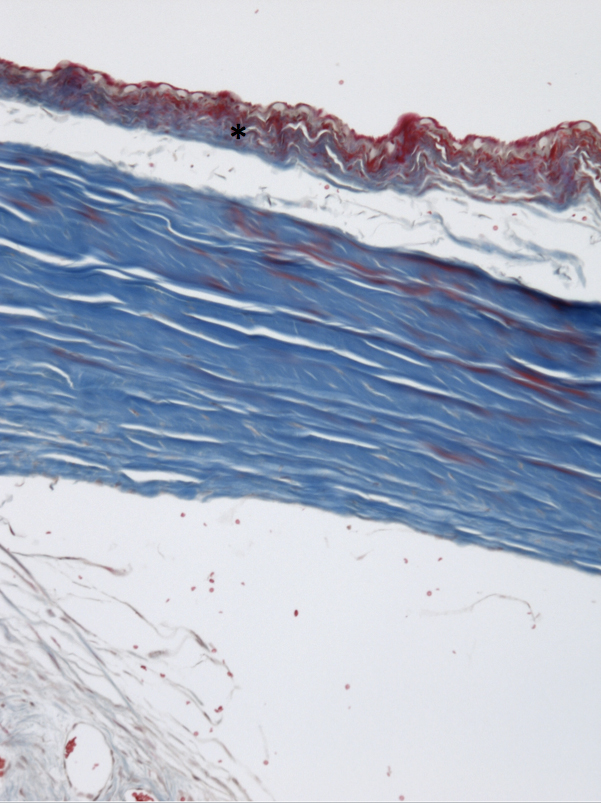

Figure 1 of SooHoo, Mol Vis 2012; 18:714-719.

Figure 1. MMC-treated tissue was noted to have less collagen deposition (asterisk) with Masson Trichrome stain compared to Ozurdex®- or BSS-treated eyes as well as loss of normal distribution of goblet cells in all sections (10× magnification).